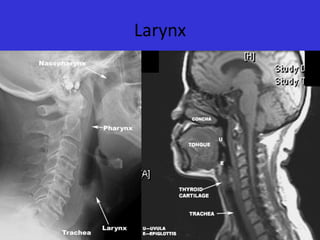

Larynx